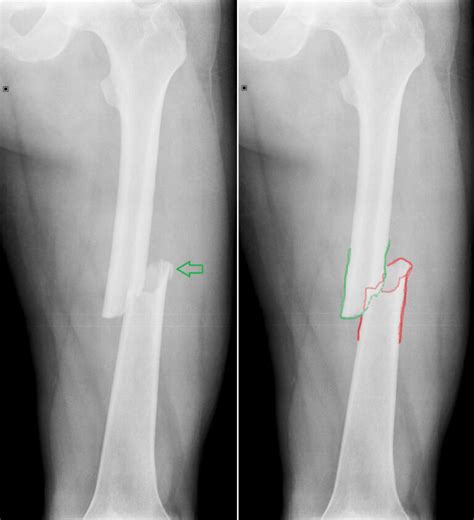

- Zlomeniny dlhých kostí (stehennej a ramennej): Sú prejavom hrubého násilia a dnes sa takmer nevyskytujú.